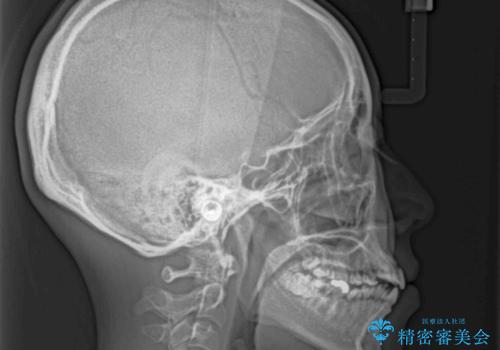

IPR(歯と歯の間を削る)と側方拡大では口の閉じにくさは改善できそうになく、一方で抜歯矯正を行うほどの突出感は認められませんでした。

親知らずを全て抜去し、歯列全体を後方に移動させることで口元の閉じにくさいを改善していくこととしました。